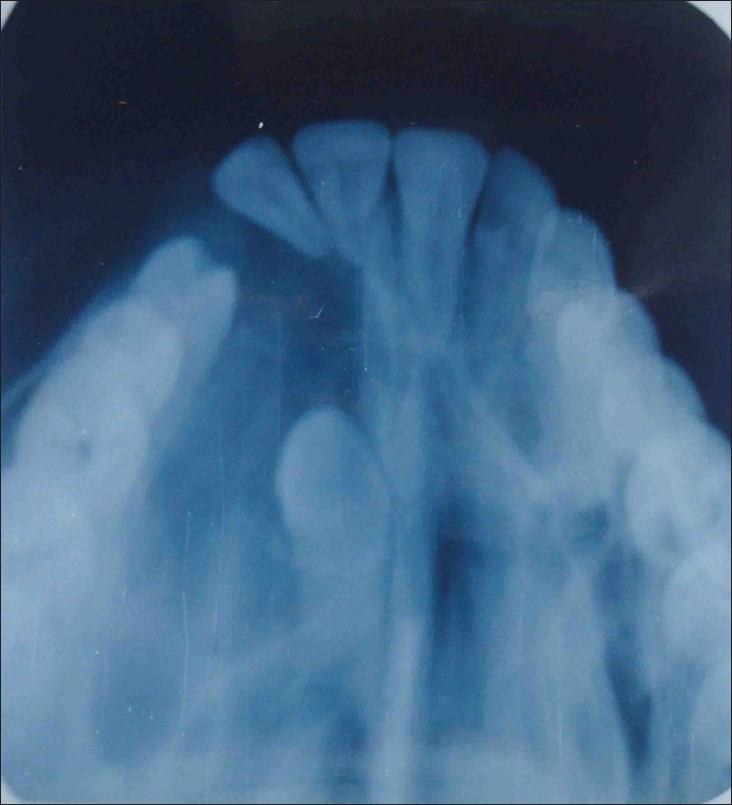

Maxillary antral mucocoele caused by ectopic canine tooth in maxillary sinus |

p. 83 |

Chandra D Dwivedi, Shweta Dwivedi, Thakur Prasad Chaturvedi, Naresh Sharma DOI:10.4103/2278-9626.106827 A seventeen year old male presented with a 5 month history of left sided purulent rhinorrhoea and left facial pain. Occlusal view X-ray of maxilla showed the presence of an ectopic canine in the leftt anterosuperior aspect of the maxillary sinus entrapped in soft tissue. Surgical removal of the tooth and the diseased antral tissue was undertaken via a Caldwell-Luc procedure with resolution of symptoms. |